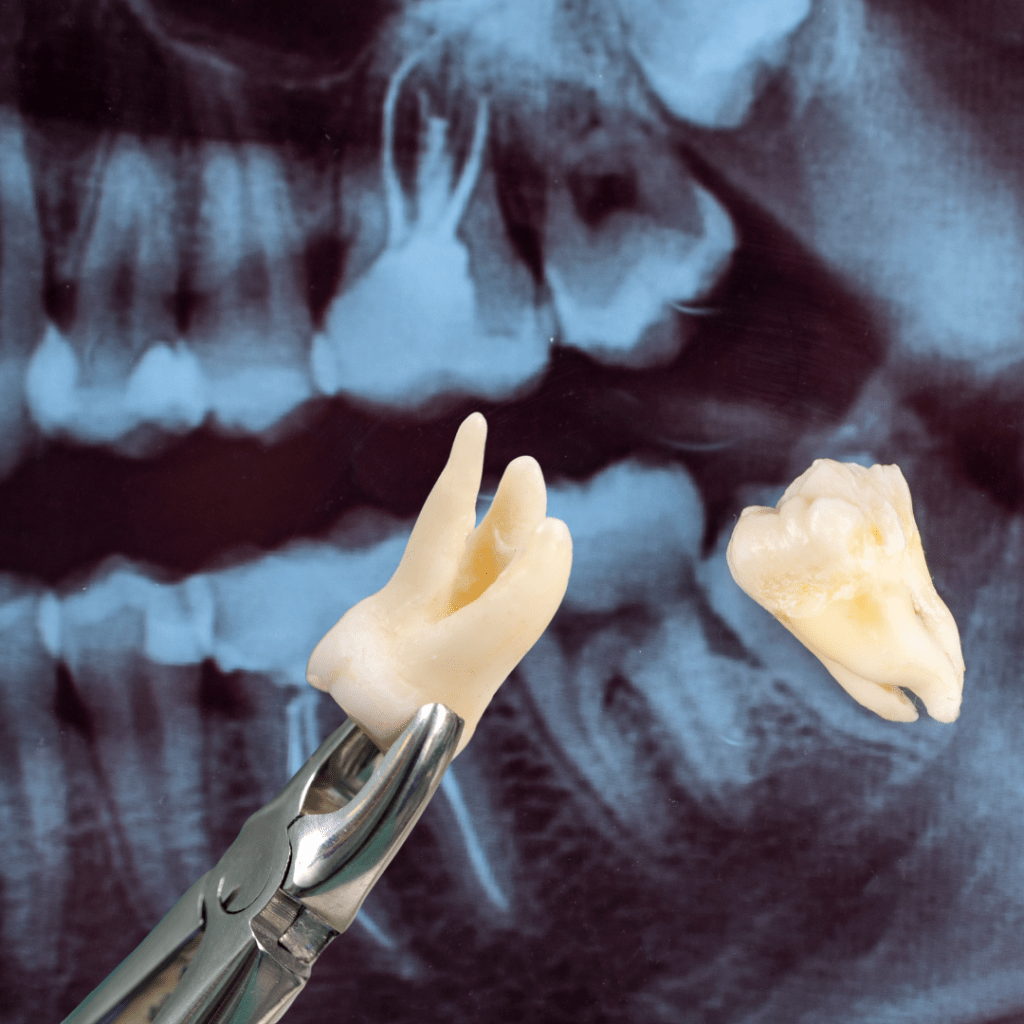

CIRUGIA ORAL

- Exodoncia de terceros molares

- Exodoncia de restos radiculares

- Exodoncias de dientes previamente endodonciados

- Ventanas quirúrgicas

- Enucleación de quistes